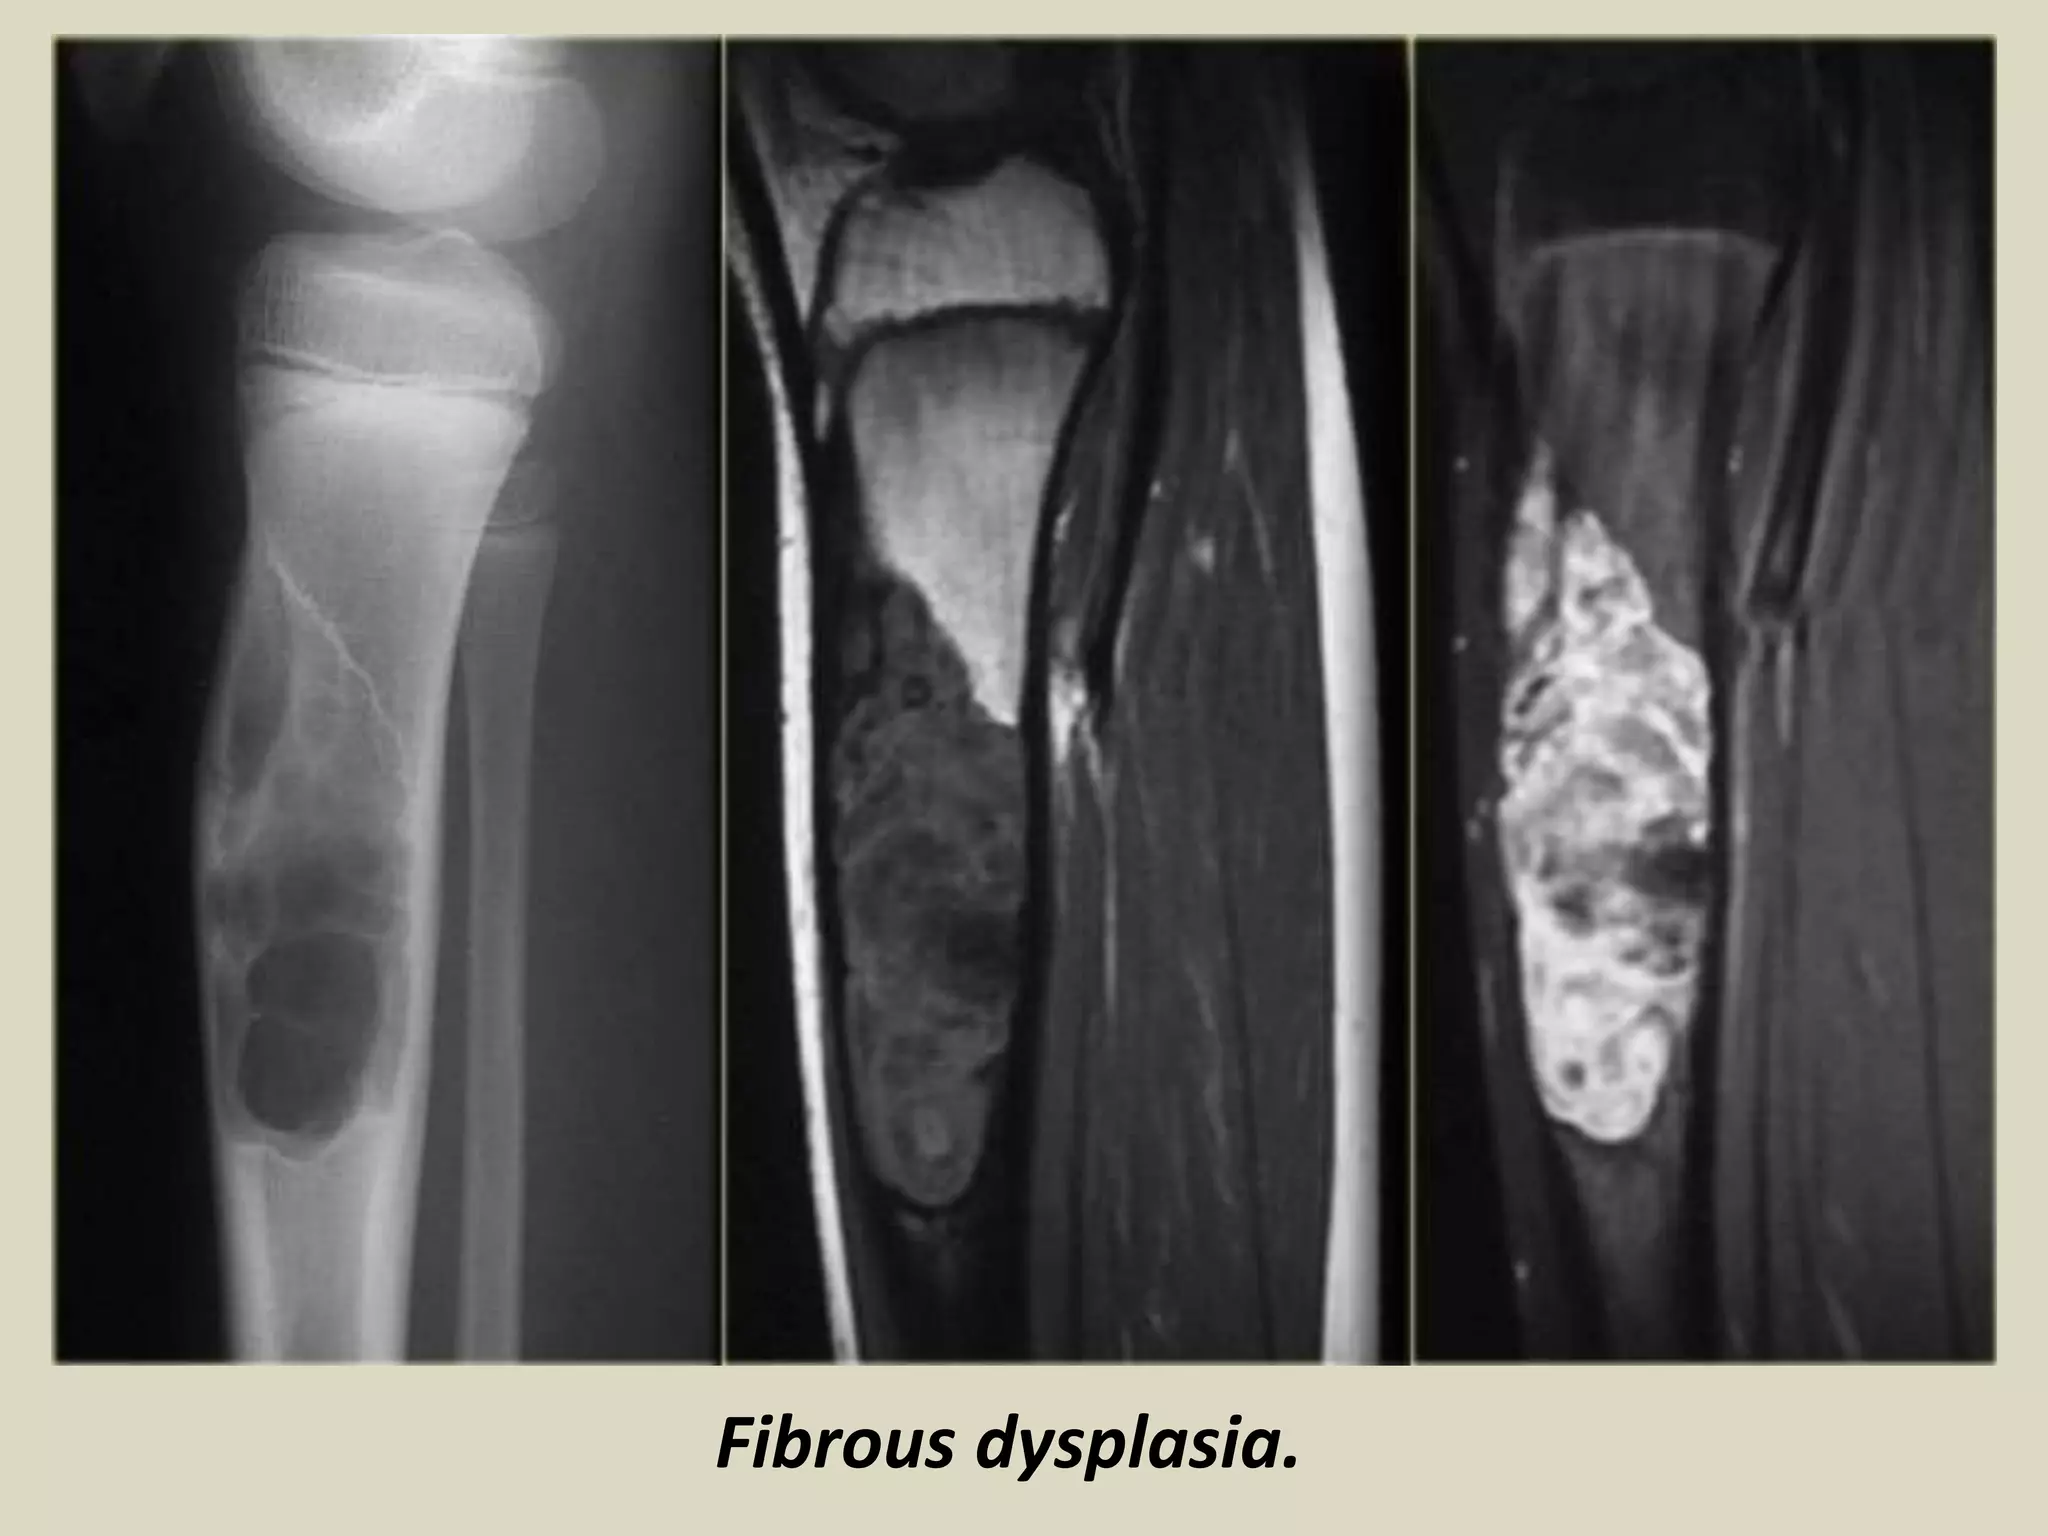

FIBROUS DYSPLASIA

Definition:

- Benign medullary fibro-osseous lesion which may involve one (monostotic) or more bones

(polyostotic).

Epidemiology: - Children and adults

- Monostotic solitary lesion most common 70-80%

- No sex predilection.

Sites of involvement:

- Gnathic (jaw) bones most common

- Long bones are more often involved in woman

- Ribs and skull are favored sites for man.

- Monostotic form, about 35% involve the head, 1/3 tibia and femur, and rest 20% ribs.

- Polyostotic form, the femur, pelvis and tibia are more common involved

Clinical findings:

- Fibrous dysplasia may present in monostotic or polyostotic form.

- Polyostotic form can be confined to one extremity or one side of the body or be diffuse.

- Polyostotic form often manifest earlier in life than the monostotic form.

- FD is often asymptomatic but pain and fractures may be part of clinical spectrum.

- FD may be associated with oncogenic osteomalacia.

-Imaging:

- Non aggressive geographical lesion with a ground glass matrix.

- In the appendicular skeleton, the margins are usually well defined and surrounded by

a rim of sclerotic bone.

- FD in the craniofacial skeleton seems to be less well defined and blends with surrounding bone.

Fibrous dysplasia.